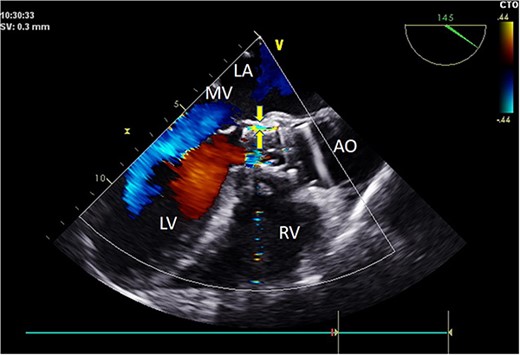

Preoperative TEE revealed moderate calcification, leaflet thickening, and hypertrophy of the tricuspid aortic valve (Fig. 1). The valve leaflets were restricted in motion, with a calculated maximum valve area of ~1.1 cm2 using the continuity equation. Color Doppler flow imaging demonstrated moderate aortic regurgitation. Additionally, a 9 mm-wide ASD was found in the mid-septal region (Fig. 2), with residual lengths on either side. Color Doppler revealed left-to-right shunting at the atrial level.

Intraoperatively, after self-expanding the aortic valve, TEE monitoring confirmed excellent cardiac function, disappearance of aortic valve regurgitation, secure anchoring of the aortic valve prosthesis, and no obstruction to the mitral valve leaflets or coronary ostia. The aortic valve velocity and pressure gradient upstream of the valve decreased compared to preoperative values, with a maximum velocity of 166 cm/s and a pressure gradient of 11 mmHg (Fig. 3). However, a periprosthetic leak with a residual width of ~4.5 mm was observed at the self-expanding valve’s interface with the native annulus (Fig. 4). Based on preoperative data, the decision was made to re-expand and reshape the prosthesis. Postdilation, TEE monitoring showed a reduction in the periprosthetic leak to 1.5 mm (Fig. 5), a significant improvement compared to predilation. Following satisfactory self-expansion results, the planned percutaneous ASD closure procedure was performed under ultrasound guidance. The closure device was securely positioned in the atrial septum, and TEE examination showed no deformation or impingement of the self-expanding valve (Fig. 6). Atrial shunting was eliminated, and the outcome exceeded expectations.

Intraoperative TEE: Long-axis aorta section shows a 1.5 mm-wide paravalvular blood flow beam, demonstrating significant improvement. Abbreviations: LA - left atrium; LV - left ventricle; RV - right ventricle; AO - aorta; MV - mitral valve.